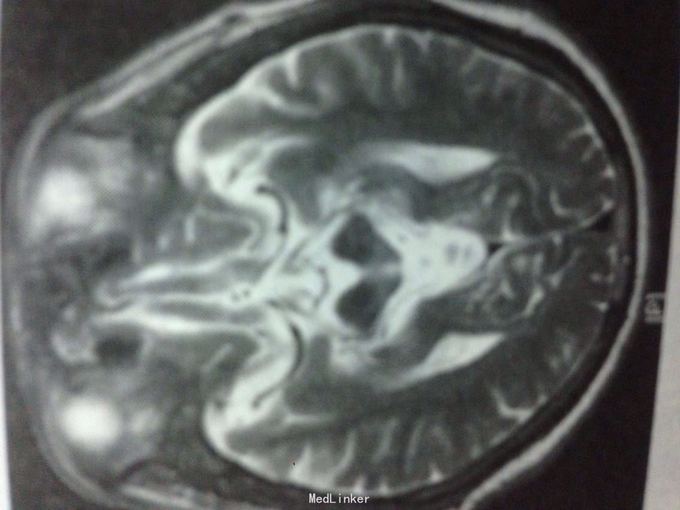

查体:神智清楚,对答切题,言语不清,双眼球上视、下视明显障碍,四肢肌张力偏高,余查体未见明显异常。 门诊头颅CT示:脑萎缩,脑白质变性。 颅脑MR示:T1矢状位中脑上部呈鸟嘴状改变,整体影像符合进行性核上性麻痹表现。